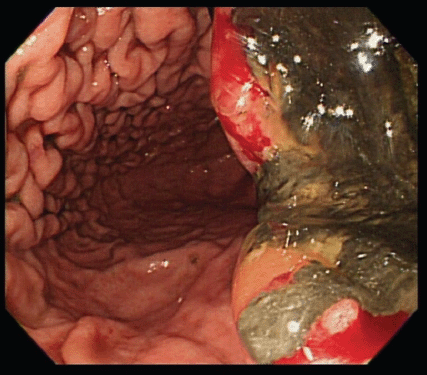

An upper gastrointestinal tract endoscopy led to the finding of a giant gastric ulcer over lesser curvature of the stomach (Figure 2). Pathology study of the biopsy specimen from the ulcer confirmed the nature of a poorly differentiated carcinoma (Figure 3) positive for cytokeratin AE1/AE3, with morphology patterns in favour of a gastric rather than a pancreatic origin. Immunohistochemical staining afterwards revealed only moderately positive expression of dihydropyrimidine dehydrogenase (DPD) (Rabbit monoclonal DPYD EPR8811: ab134922, Abcam, Cambridge, UK) (Figure 4) and totally negative expression of Bcl-2 (Clone bcl-2/100/D5, NovocastraTM HD, Leica Biosystems, UK) (Figure 5).

Figure 2. A giant gastric ulcer over lesser curvature of stomach (right half of the figure) revealed by upper gastrointestinal tract endoscopy.